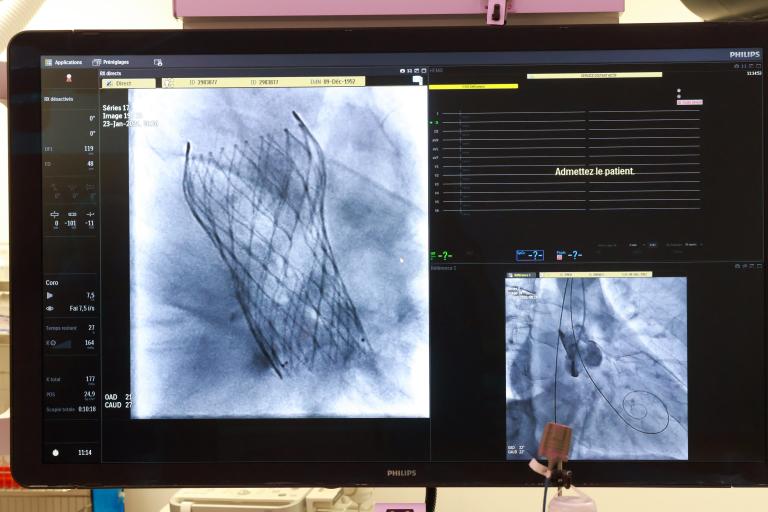

Le CHU de Clermont-Ferrand franchit une nouvelle étape dans la prise en charge des patients souffrant de sténose aortique en rejoignant les tout premiers centres français à implanter la nouvelle valve Evolut™ FX+ de Medtronic, testée lors de sa semaine d’avant‑première nationale. Cette avancée marque un tournant important pour la cardiologie interventionnelle et témoigne de l'engagement continu de notre établissement envers l’innovation au service du patient.

La valve Evolut™ FX+ représente l’évolution la plus récente des dispositifs de TAVI (Transcatheter Aortic Valve Implantation), une technique mini‑invasive permettant de remplacer la valve aortique sans chirurgie à cœur ouvert.

La nouvelle conception inclut trois fenêtres quatre fois plus grandes dans le stent, offrant une meilleure vue et un contrôle accru durant la procédure. Cette évolution améliore la précision du geste pour les cardiologues interventionnels.

L’agrandissement des mailles de la structure métallique permet désormais un accès nettement simplifié aux artères coronaires pour de futures interventions.